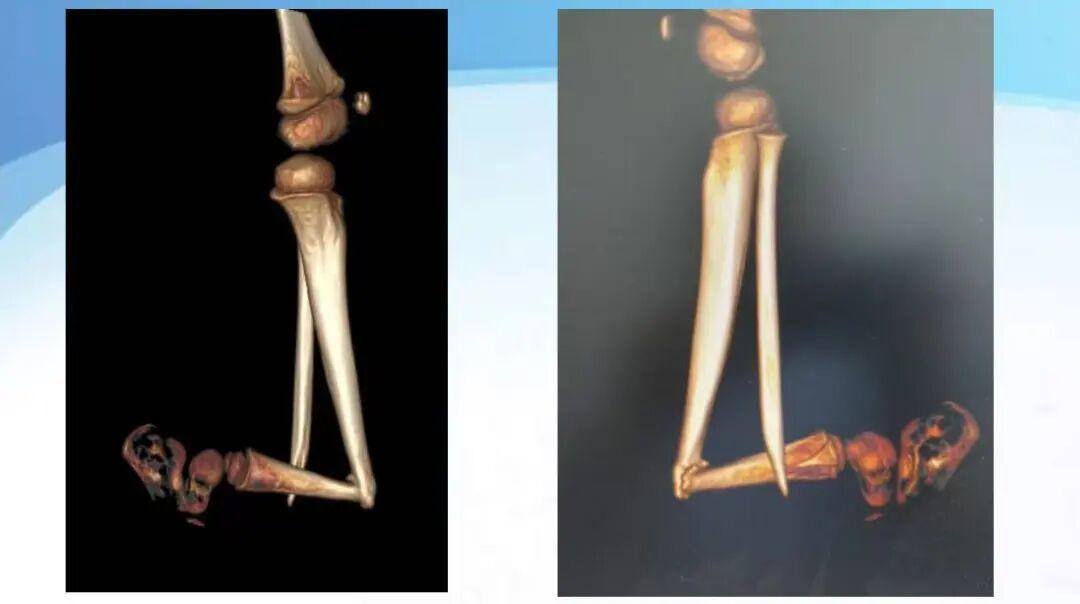

术前

术后

出院后,花花定期回院复查。经过一段时间的努力,复查影像显示她的骨折已达到临床愈合,左小腿力线恢复良好。如今,7岁多的花花已告别了跪地行走的日子,不仅能平稳站立、自如步行,还能与小同伴一起奔跑、游戏,顺利融入校园生活。这场爱心手术,不仅重塑了她的小腿,更托起了她重新站立的童年。